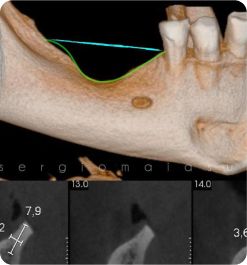

IMERSÃO EM CIRURGIA GUIADA

Coordenação: Paulo Abdalla Saad

• Teórico

• Prático

• Demostrativo

IMERSÃO THE GRAFT COM ÊNFASE EM RECONSTRUÇÕES ÓSSEAS

Coordenação: Dr. Sérgio Maia

Público alvo: Cirurgiões dentistas Implantodontistas, Periodontistas e Bucomaxilofaciais.

Curso prático de 3 dias | Material Incluso para todas as Práticas.